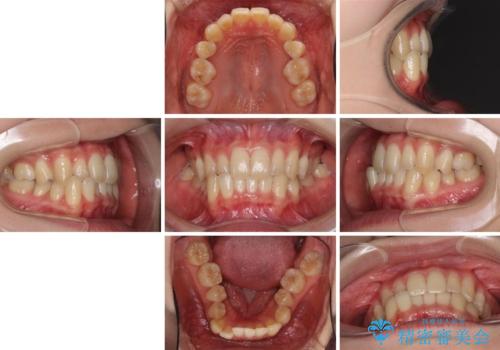

奥歯の反対咬合 上顎骨を拡大してインビザラインで矯正

- 奥歯の反対咬合を気にして来院された患者様です。

反対咬合は上顎骨の幅が下顎骨よりも小さいことが原因なので、拡大装置により骨幅を広げて上下関係を改善し、その後インビザラインにて歯並びを整えることとしました。